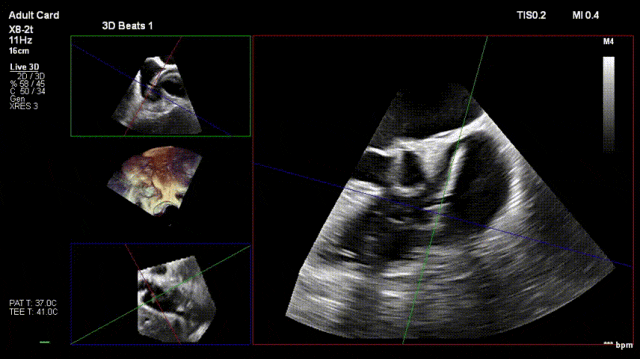

Following a comprehensive multi-dimensional evaluation by the cardiology team at Jiangsu Provincial People's Hospital, and in consideration of the patient's tricuspid valve lesion characteristics and anatomical structure, a precise surgical plan of dual-clip K-Clip® implantation was formulated to achieve optimal therapeutic outcomes. A 12T K-Clip® was implanted at the posterior tricuspid annulus, and a 14T K-Clip® was implanted at the anteroposterior commissure. Through precisely positioned dual-point implantation, this procedure effectively reduces the tricuspid annulus area and enhances leaflet coaptation, directly alleviating tricuspid regurgitation at the anatomical level and laying a critical foundation for the patient's postoperative recovery.

2. Steer and rotate the delivery system toward the target; advance and deploy the anchoring screw under 3D MPR plane guidance

3. After adjusting orientation, position the clamping arms for landing

4. The same procedure is performed for the second clip; the clip morphology is stable under ultrasound